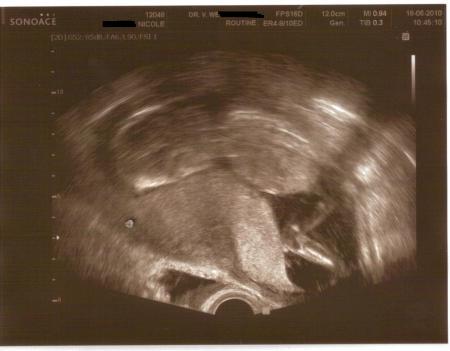

Huhu *piep* mir gehts nicht besonders doll.. immernoch Blutungen... Baby wegen Plazentablutung etwas zurück, hat aber gerade wieder aufgeholt und ist jetzt 12 cm (ich bin bei 17+3 heute). Haben Angst, dass Flöckchen doch vor der 24ssw kommen könnte und war schon 4 mal im Krankenhaus,.. wir müssen einfach darauf hoffen, dass sich alles bessert und Flöckchen durchhält... Das Kleine ist tapfer und gibt nicht auf... Blutgerinnungsambulanz will mich nun auch regelmäßig sehen und muss Blut abgeben wie am Fließband... TSH endlich wieder unter Kontrolle bei 0,61. Muss immernoch liegen und kanns aber nicht mehr weil der Blutdruck zu stark sinkt... so ist Kind dann unterversorgt.. muss einen schmalen Grad gehen.. Wir wären für Daumen dankbar und es tut mir leid, dass ich nach so langer Zeit mich jetzt erst wieder melde, aber es war soviel los und ich versuch wieder regelmäßig dazu sein. Am nächsten Freitag bin ich wieder zur nächsten regulären Untersuchung geladen (alle 2 Wochen wenn nicht zwischendrin wieder Blutungen und Probleme auftreten). Alles Liebe Nicole / Feenstaub226

Bild zu

Bei den Letzten Untersuchungen haben wir garnicht nach dem Geschlecht nachgesehen.. das war einfach nicht wichtig.. ich habe Risse im Gebärmutterhals und die werden ständig vermessen und auch die Hämatome davor... Ich bin jedesmal einfach nur erleichtert das Flöckchen sich bewegt Schluck auf hat und winkt und das Herz brav schlägt... Ich sage immer: es wird gewickelt was auf den Tisch kommt.. hauptsache es schafft es bis dahin und ist gesund... Wir wissen nicht wieviel Schaden die Plazentablutung hinterlassen hat und werden das erst sehen wenn es noch ein bischen größer ist... Ich wünsche so eine Schwangerschaft niemandem auf der Welt... und doch muss ich dankbar sein, überhaupt es bis hierher geschafft zu haben. Danke für Eure Daumen.. Nächsten Termine: 28.06.2010 UniKlinik Heidelberg 02.07.2010 Fa 16.07.2010 Fa